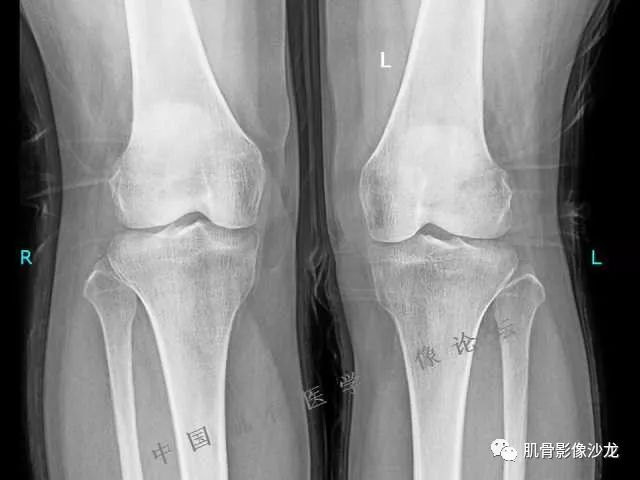

雪舞 : 股骨下端,皮质下偏心性溶骨性破坏,分叶状,T2混杂高信号。无明显软组织肿块。X片未见异常。

雪舞 第一例位置典型,但是限于资料原因,未能明确是否有钙化,周围也未见软组织肿块,骨膜反应

雪舞 :不过T2高信号,分叶状还是要想到软骨肉瘤,毕竟典型位置,骨肿瘤排名第3的软骨肉瘤